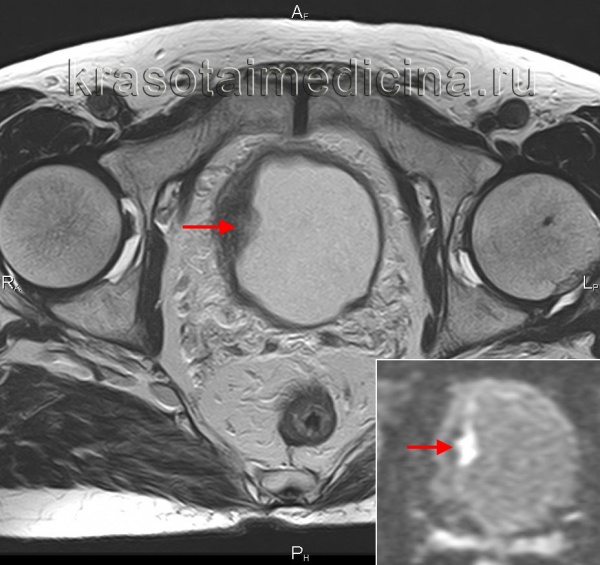

3. МРТ при плоскоклеточном раке мочевого пузыря:

• Опухоль обладает умеренной интенсивностью сигнала на Т1 и Т2

• Отмечается ее раннее контрастирование

• Постконтрастные последовательности в режиме подавления сигнала от жира являются исключительно полезным методом обнаружения околопузырного роста (ТЗЬ)